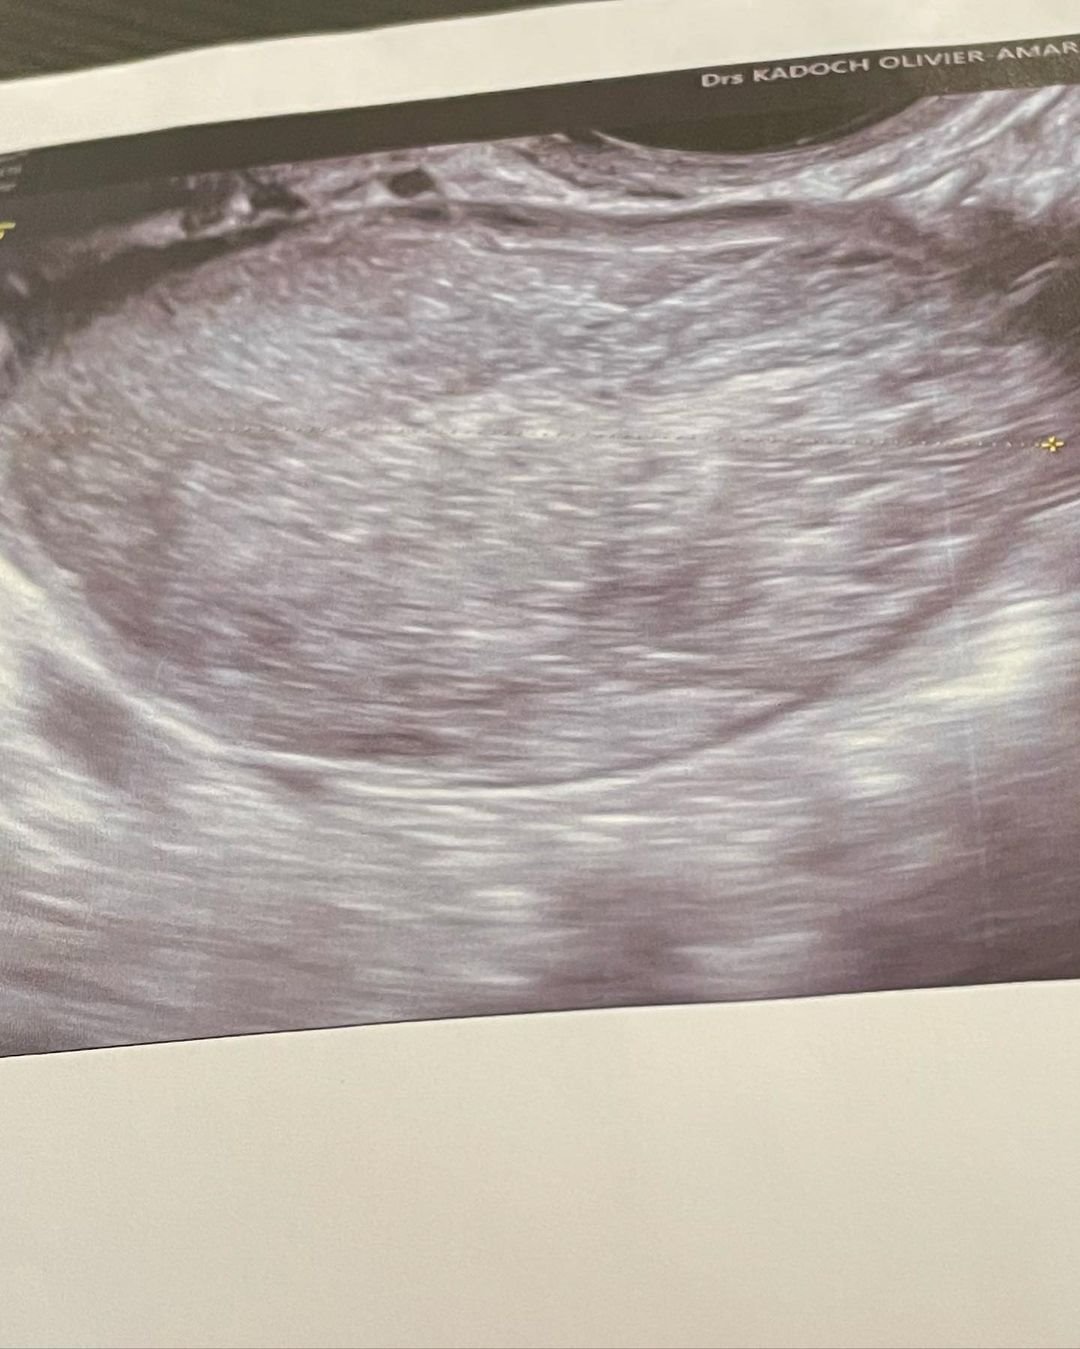

"Iz ovog iskustva sam naučila da, kada telo boli, ne sme se to ignorisati, već treba povesti računa, treba obići različite lekare i ne odustati sve dok neko od njih ne otkrije problem i ne reši ga. Čak i najmanji bol može da krije nešto mnogo važnije", napisala je manekenka. Toliko je želela da njeno iskustvo bude od pomoći drugim ženama  da je čak objavila i snimak svog ultrazvuka i pripreme za operaciju!

Nekad najlepša devojčica na svetu obišla je brojne lekare dok joj najzad nije otkrivena cista na jajniku.  Foto: Instagram / thylaneblodeau